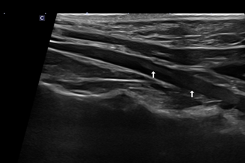

환자의 심장초음파 사진(RPS long axis view 상 좌심방 너비 25.6mm 심한 확장)/출처: 24시 동탄리더스동물의료원

좌심방의 수축력(LA FS)은 6.5%로, 정상 기준(25% 이하)에 비해 현저히 저하된 상태였습니다. 이는 좌심방이 혈액을 밀어내는 기능이 크게 떨어졌다는 의미입니다.

환자의 심장초음파 사진(좌심방 수축력 6.5% 심한 감소 (정상 25%이내)) / 출처: 24시 동탄리더스동물의료원